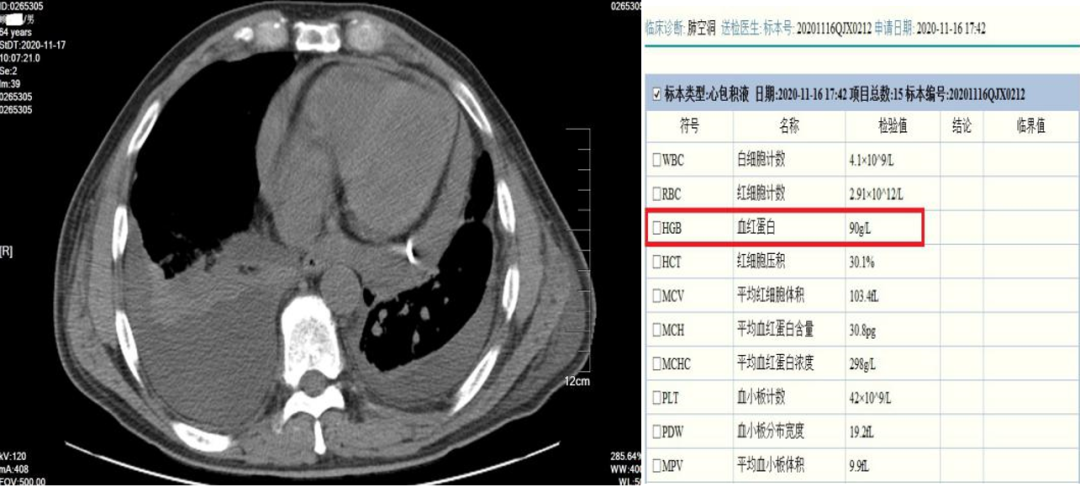

一个月以后复查的CT结果显示,患者好转,心包积液消失,两侧胸水消失,病灶仍然存在。

复查CT对比图